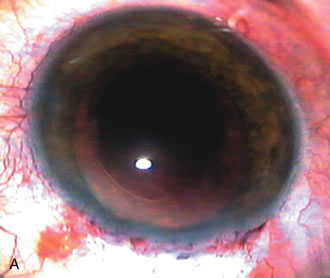

Fig. 3. Partial bleb failure following clear corneal phacoemulsification with foldable IOL. A. Preoperative bleb appearance prior to temporal lens extraction. Preoperative IOP was 12 mm Hg on no antiglaucoma medications. Time from 5-FU trabeculectomy surgery to lens extraction was one year. B. Bleb appearance 2 months after clear corneal cataract surgery with topical anesthesia. Following lens extraction, increased vascularity was noted along with decreased size of the filtering bleb. IOP increased to 20 mm Hg as early as 2 weeks after surgery, necessitating topical antiglaucoma therapy. C. High magnification view of bleb before lens extraction demonstrates diffuse pale bleb. D. High magnification view of bleb 2 months after surgery. There are vessels surrounding the nasal side of the bleb and the overall bleb size is smaller.